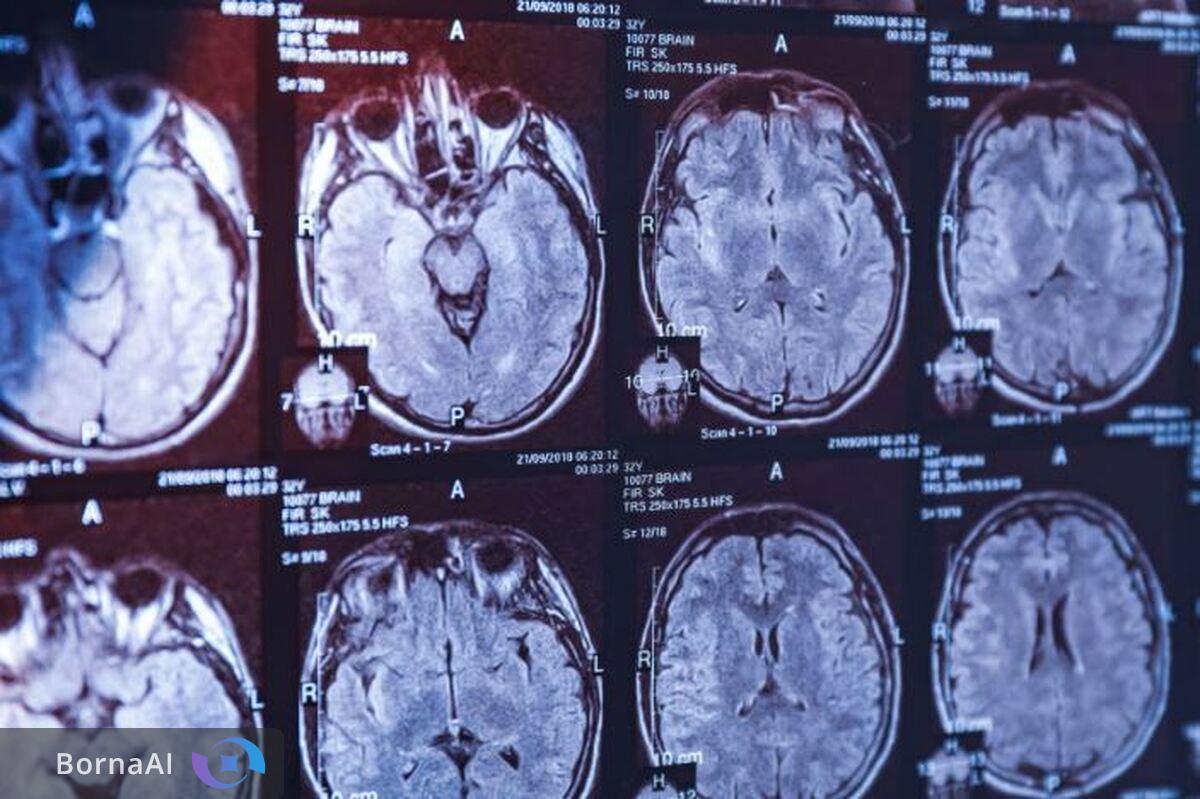

وی در ادامه پاسخ به سوال برنا گروه دوم فناوریهای شناختی را فناوریهای نقشهبرداری مغزی یا "نورومپینگ Neuromapping" عنوان کرد و گفت: این فناوریها طیف گستردهای از تجهیزات را شامل میشود؛ از دستگاههای ثبت سیگنالهای مغزی گرفته تا تجهیزات پیشرفتهتر مانند ثبت عمقی سیگنالها و دستگاههای تصویربرداری پیشرفتهای نظیر MRI، PET و MEG که برای تحلیل، ثبت و پردازش تصاویر مغزی مورد استفاده قرار میگیرند.

ارتقای دستگاههای MRI بالینی با نرمافزارهای بومی

پورعباسی در ادامه به وضعیت دستگاههای تصویربرداری بزرگ و بالینی مانند MRIهای مرسوم اشاره کرد و گفت: در این حوزه دستاورد اصلی فناوران داخلی توسعه نرمافزارهای متناسب با این دستگاهها و همچنین دستیابی به دانش فنی اورهال و بهروزرسانی تجهیزات تصویربرداری است که این توانمندی در کشور وجود دارد.

وی به برنا گفت: نکته جالب توجه این است که فناوران داخلی با استفاده از نرمافزارهای بومی تصاویری که از دستگاههای MRI سه تسلا استخراج میشود را با کیفیتی معادل MRI هفت تسلا تحلیل و گزارش میکنند.

دبیر ستاد علوم و فناوریهای شناختی توضیح داد: بهعبارت دیگر با توسعه یک نرمافزار بومی این امکان فراهم شده است که از دستگاههای تصویربرداری سه تسلا تصاویری با کیفیت بسیار بالاتر تهیه شود که این موضوع یک فناوری بسیار ارزشمند محسوب میشود و هماکنون در اختیار درمانگران، پزشکان و متخصصان کشور قرار دارد.